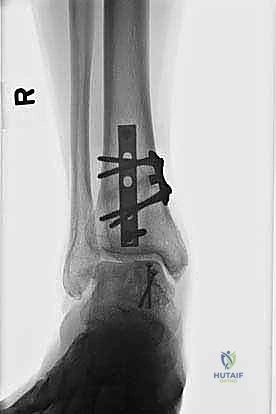

- التصوير بالأشعة السينية (X-rays): الخطوة الأولى لاستبعاد الكسور الكبيرة وتقييم المحاذاة العامة للعظام. قد تظهر الأشعة السينية الآفات الكبيرة، لكنها غالباً ما تفشل في إظهار التلف الغضروفي المبكر.

- التصوير المقطعي المحوسب (CT Scan): ضروري جداً للآفات الكبيرة. يوفر الـ CT صورة ثلاثية الأبعاد للعظم، مما يساعد الجراح في التخطيط الدقيق لعملية قطع العظم وحجم الطعم المطلوب زراعته.

الغوص العميق في جراحة الطعم الخيفي الهيكلي (Structural Allograft Reconstruction)

يهدف هذا الإجراء العبقري إلى استبدال الغضروف والعظم التالفين والميتين بنسيج سليم تماماً مأخوذ من متبرع متوفى (طعم خيفي - Allograft). هذا الطعم يتم تعقيمه وحفظه في بنوك الأنسجة العالمية وفقاً لأعلى المعايير الطبية الصارمة لضمان خلوه من أي أمراض معدية والحفاظ على حيوية الخلايا الغضروفية.

- الترميم التشريحي الحقيقي: يسمح باستعادة الشكل الهندسي الدقيق لعظم الكاحل، بما في ذلك المنحنيات المعقدة لكتف التالوس.